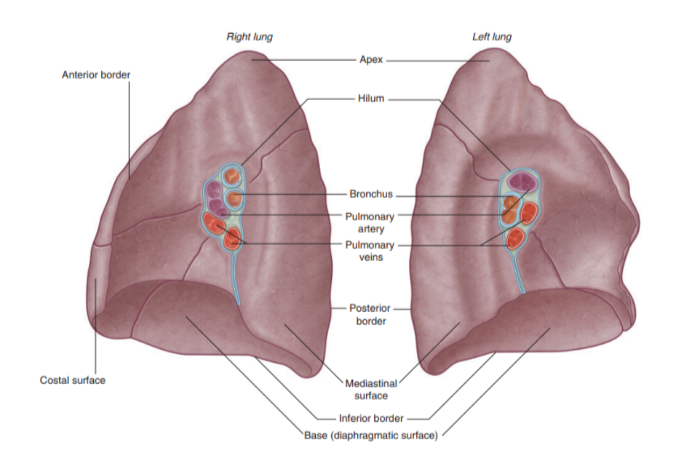

Landmarks recognizable in the lung

The base —

Situated on the diaphragm

The apex —

Projects above rib 1 & into root of neck

Costal surface —

Adjacent to ribs + Intercostal spaces

Mediastinal surface —

Lies against mediastinum anteriorly & vertebral column posteriorly — this surface contains the hilum

3 borders —

Inferior border —

Sharp, separates the base from the costal surface

Anterior border —

Sharp, separates costal surface from medial surface

Posterior border —

Smooth & rounded, separates costal surface from medial surface

We can also recognize certain indentations corresponding to surrounding structures

Root + hilum

The root —

A short tubular collection of structures attaching each lung to structures in the mediastinum

Covered in a sleeve of mediastinal pleura reflecting onto the lung surface as visceral pleura

Originates the pulmonary ligament — thin blade-like pleural fold projecting from the root towards the mediastinum, functioning to stabilize the position of the inferior lobe

The hilum —

The region outlined by this pleural reflection on the medial lung surface — where structures enter & leave

Structures we can find in each root & hilum —

Pulmonary artery

2 Pulmonary veins

Main bronchus

Bronchial vessels

Nerves

Lymphatics

The pulmonary artery is in most cases found at most superior portion of the hilum, while the pulmonary veins are inferior & the bronchi are posterior

On the side side however, the lobar bronchus to the superior lobe branches from the main bronchus in the root, unlike on the left where it branches in the lung itself superiorly to the pulmonary artery